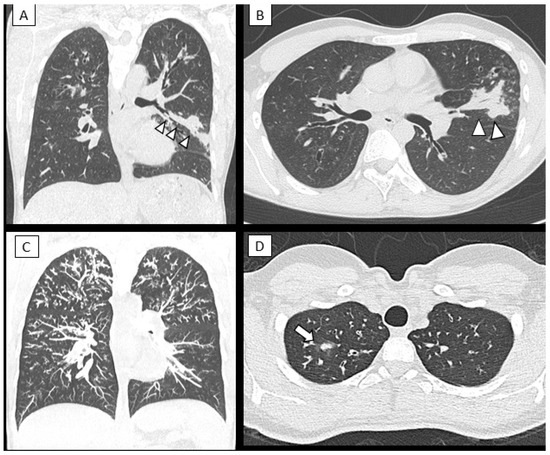

- Lv, Q.; Elders, B.B.L.J.; Warris, A.; Caudri, D.; Ciet, P.; Tiddens, H.A.W.M. Aspergillus-related lung disease in people with cystic fibrosis: Can imaging help us to diagnose disease? Eur. Respir. Rev. 2021, 30, 210103. [Google Scholar] [CrossRef]